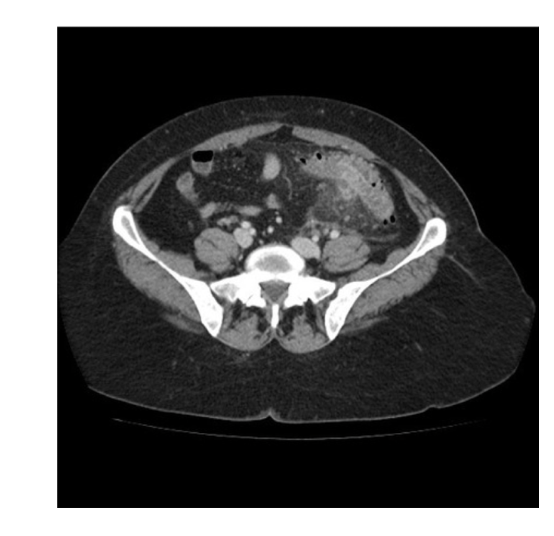

What is the pathology?

• Diverticulosis: pockets of air

branching from the bowel

• Thickening of the lumen wall

• Leaking of gas into Abdo cavity